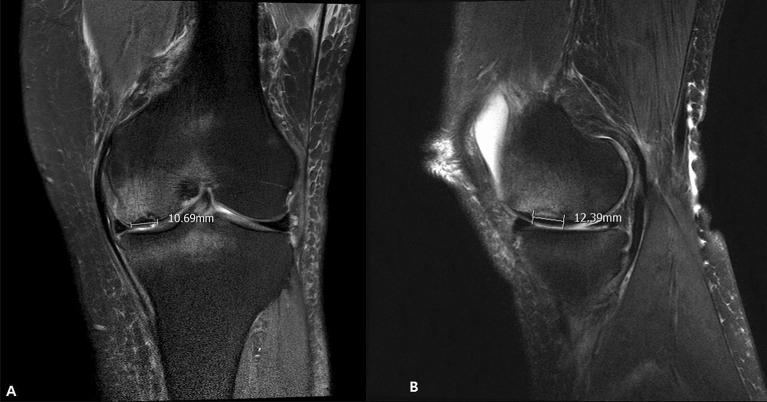

Subchondral insufficiency fracture of the knee (SIFK) causes acute knee pain in adults and often requires surgical management. Unicompartmental knee arthroplasty (UKA) and total knee arthroplasty (TKA) are the two most common surgical treatments for SIFK. While both UKA and TKA have their advantages, there is no consensus for SIFK localized on the medial compartment. We hypothesized that patients with SIFK treated with UKA would show superior patient-reported outcomes compared to those who underwent TKA. A total of 90 patients with SIFK located medially were included in the TKA (n = 45) and UKA (n = 45) groups. Size of SIFK lesions were measured on MR images. Patient reported outcomes in the form of the Western Ontario and McMaster Universities Osteoarthritis Index (WOMAC), Hospital Special Surgery (HSS) scores, and Knee Society Scores (KSS) were assessed preoperatively, postoperative 6, 12 months, and at the final follow-up. There were no differences in the size of the SIFK lesion between two groups. At 6 months, WOMAC score was better in the UKA group than the TKA group (p < .01). Both groups had a significant improvement in WOMAC, HSS, and KSS scores at the final follow-up compared to preoperative scores. The UKA group had better range of motion of the knee preoperatively and postoperatively than the TKA group (p < .01 and p < .01). UKA group showed a higher relative risk than the TKA group in terms of complications (RR = 3.0) but with no statistical significance (P = 0.31). Unicompartmental arthroplasty and total joint arthroplasty can produce successful outcomes in patients with SIFK with proper patient selection, regardless of the size of SIFK lesion.

膝关节下骨不全骨折(SIFK)可导致成年人急性膝关节疼痛,通常需要手术治疗。单髁膝关节置换术(UKA)和全膝关节置换术(TKA)是治疗 SIFK 的两种最常见的手术方法。虽然 UKA 和 TKA 都有各自的优势,但对于位于内侧间室的 SIFK,尚无共识。我们假设,接受 UKA 治疗的 SIFK 患者的患者报告结果(PRO)优于接受 TKA 治疗的患者。共纳入 90 例内侧 SIFK 患者,分别纳入 TKA(n=45)和 UKA(n=45)组。在 MR 图像上测量 SIFK 病变的大小。采用 Western Ontario and McMaster Universities Osteoarthritis Index(WOMAC)、Hospital Special Surgery(HSS)评分和 Knee Society Scores(KSS)评估患者报告的结果,分别在术前、术后 6 个月、12 个月和最终随访时进行评估。两组 SIFK 病变的大小无差异。在 6 个月时,UKA 组的 WOMAC 评分优于 TKA 组(p<0.01)。与术前评分相比,两组在最终随访时 WOMAC、HSS 和 KSS 评分均有显著改善。UKA 组术前和术后膝关节活动度均优于 TKA 组(p<0.01 和 p<0.01)。UKA 组的并发症相对风险高于 TKA 组(RR=3.0),但无统计学意义(P=0.31)。对于适当的患者选择,无论 SIFK 病变的大小如何,单髁关节置换术和全关节置换术都可以为 SIFK 患者带来成功的结果。